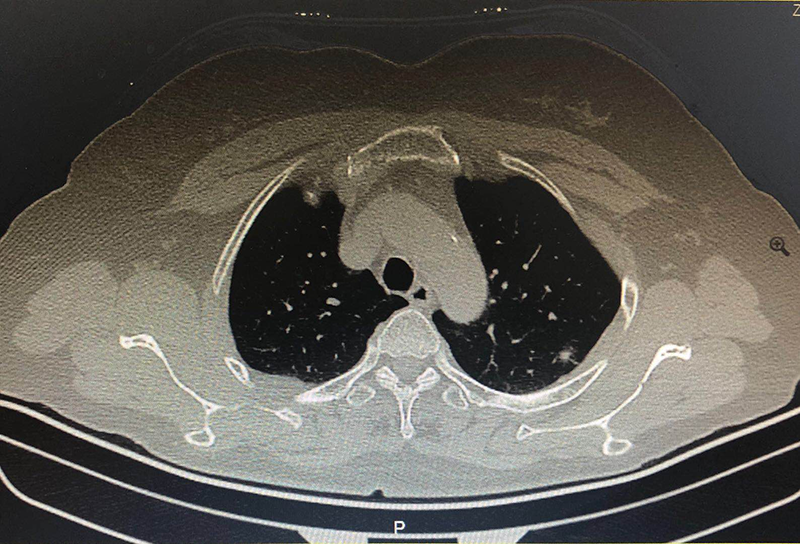

海宁的吴女士(化名)因胸闷、咳嗽久不见好转,进行了胸部CT检查,结果在肺部发现了35px的结节,并且不排除肺癌可能。

知道结果的吴女士十分担心,有医生建议先进行手术比较保险,但王剑飞认为应先进一步确诊,不着急手术。后经过一段时间的消炎、雾化吸入、中药调理等治疗,一个月后,吴女士的结节缩小至6mm,一切症状都显示并没有癌变危险,保持三个月随访即可。这令吴女士安了心,也免除了手术的痛苦。

王剑飞提醒市民,发现肺部结节时先不要着急,一定要到专科找专家医生咨询。部分肺部结节确实很难鉴别良恶性,但并不建议贸然开刀,定期随访后,如果结节出现变大、变实等情况,再进行手术干预还是没问题的。